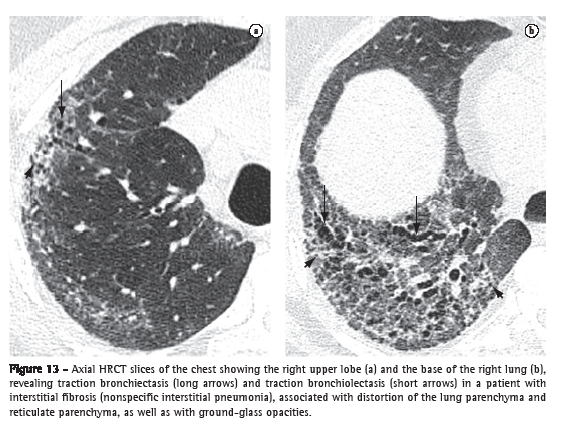

Traction bronchiectasis and traction bronchiolectasis (bronquiectasia e bronquiolectasia de tração)

Traction bronchiectasis and traction bronchiolectasis refer, respectively, to bronchial and bronchiolar dilatation secondary to the retraction of the parenchyma resulting from fibrosis (Figure 13).(3) They manifest as bronchial and bronchiolar dilatations, often irregular, associated with the distortion of the parenchyma due to fibrosis and other lung alterations (principally reticular opacities, ground-glass opacities and consolidations). They have a tubular, cystic or microcystic aspect (peripheral bronchioles), depending on the relationship between the bronchial axis or the bronchiolar axis and the CT scan slice. This last aspect can be confused with honeycombing, another alteration frequently associated with pulmonary fibrosis.(28)

Architectural distortion (distorção da arquitetura)

Architectural distortion is characterized by displacements in the path and/or distortions in the morphology of anatomical structures such as bronchi, vessels, fissures, or interlobular septa; it is usually related to caused by diffuse parenchymal diseases, particularly interstitial fibrosis.(7) On HRCT scans, the loss of anatomical definition of the secondary lobule and the local volume reduction are considered signs of architectural distortion of the lobule and can be considered indirect signs of fibrosis (Figure 13).(3)